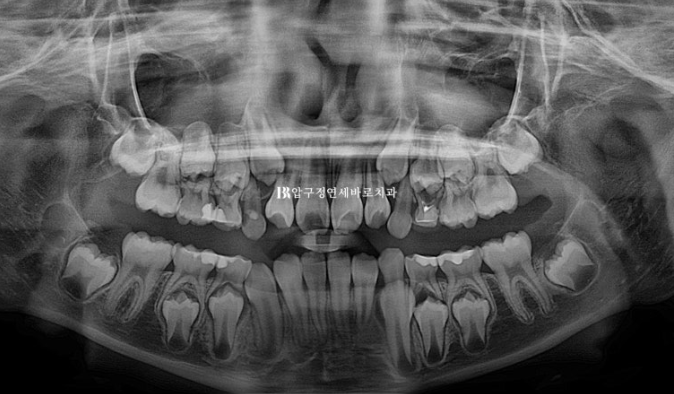

지난 치료를 요약해보면 초진 시 앞니 4개씩 나온 상황입니다.

유치가 10개나 남은 상황이나 아이들이 이 빠지고 나는 속도는 사람마다 달라 정확한 예측은 어렵습니다.

2022.09

아역배우 친구여서 보이는 철사교정 말고 인비절라인 퍼스트 어린이 투명교정 장치로 시작했습니다.

24.01

아래는 유지가 잘 되어서 문제가 없었으니 위 송곳니 날 자리가 부족해서 덧니처럼 회전이 된 채 내려오는 것이 보입니다.

덧니처럼 나와있던 송곳니는 잘 배열이 되었고 그 사이 마지막 유치 어금니 4개가 빠지고 영구치 작은 어금니가 내려오는 중입니다.

드디어 영구치열에 접어들었습니다.